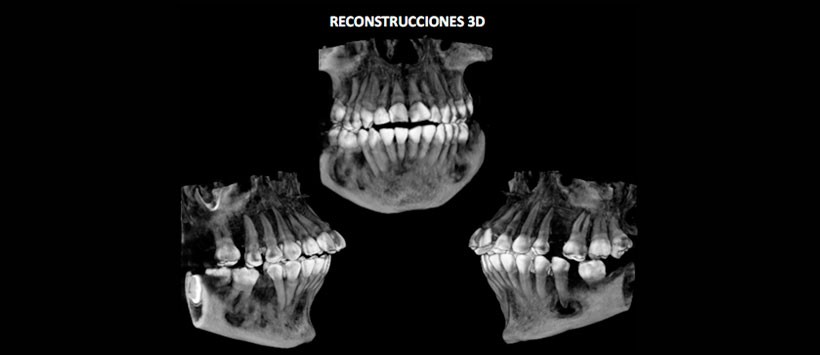

En las reconstrucciones 3D (Figura 5 y 6) se muestran las imágenes antes descritas que da la apariencia de pérdida de estructura ósea y su relación con estructuras adyacentes.